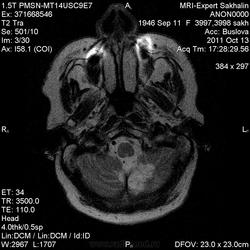

Последствия ОНМК с геморрагическим пропитыванием справа. Кистозно-атрофические изменения в левой гемисфере мозжечка (последствия ОНМК ). Множественные очаги сливного характера вещества головного мозга ( поля лейкоариоза)

Да хотела еще добавить возможно у пациента еще были лакунарные инсульты. В области базальных ядер( слева ) определяются кисты, окруженные глиозом. И на предпоследнем изображение в правой гемисфере мозжечка по- моему и также есть нмк.

Танюша, все указала-и лакунаные постишемические кисты, и кистозно-глиозные левой гемисферы мозжечка.Правая , вроде бы, не задействована в процессе.